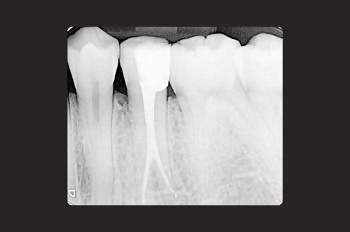

At Moltons Dental, we are committed to delivering the highest precision and care by utilising the Zeiss Extaro microscope for root canal treatments and restorative procedures.

This cutting-edge technology allows us to perform procedures with excellent precision and detail.

The Zeiss Extaro microscope enhances visibility, accuracy, and treatment outcomes, giving our patients the most reliable and predictable experience.